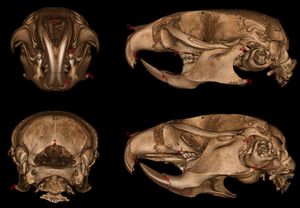

Viable Ednra Y129F Mice Feature Human Mandibulofacial Dysostosis with Alopecia (MFDA) Syndrome Due to the Homologue Mutation

Publication: Mamm Genome. 2016 Dec;27(11-12):587-98. PMID: 27671791 | PDF Authors: Sabrautzki S, Sandholzer MA, et al. Institution: Institute of Experimental Genetics and German Mouse Clinic, Helmholtz Centrum Munich, German Research Center for Environmental Health (GmbH), Neuherberg, Germany. Background/Purpose: Animal models resembling human mutations are valuable tools to research the features of complex human craniofacial syndromes. This is the first report on a viable dominant mouse model carrying a non-synonymous sequence variation within the endothelin receptor type A gene (Ednra c.386A>T, p.Tyr129Phe) derived by an ENU mutagenesis program. The identical amino acid substitution was reported recently as disease causing in three individuals with the mandibulofacial dysostosis with alopecia (MFDA, OMIM 616367) syndrome. We performed standardized phenotyping of wild-type, heterozygous, and homozygous Ednra Y129F mice within the German Mouse Clinic. Mutant mice mimic the craniofacial phenotypes of jaw dysplasia, micrognathia, dysplastic temporomandibular joints, auricular dysmorphism, and missing of the squamosal zygomatic process as described for MFDA-affected individuals. As observed in MFDA-affected individuals, mutant Ednra Y129F mice exhibit hearing impairment in line with strong abnormalities of the ossicles and further, reduction of some lung volumetric parameters. In general, heterozygous and homozygous mice demonstrated inter-individual diversity of expression of the craniofacial phenotypes as observed in MFDA patients but without showing any cleft palates, eyelid defects, or alopecia. Mutant Ednra Y129F mice represent a valuable viable model for complex human syndromes of the first and second pharyngeal arches and for further studies and analysis of impaired endothelin 1 (EDN1)-endothelin receptor type A (EDNRA) signaling. Above all, Ednra Y129F mice model the recently published human MFDA syndrome and may be helpful for further disease understanding and development of therapeutic interventions. |

Landmarks of cephalometric/mandibular measurement. In total, eight datasets were evaluated by two experienced osteologists using the distance measurement tool of 3D Slicer 4.5 . Cranial and mandibular reference points on the bone surface were selected based on previously described landmarks (De Carlos et al. 2011). |